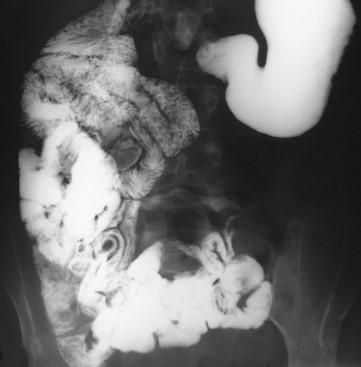

Red arrows — transition point. Multiple air-fluid levels (Courtesy Dr. V. Penopoulos)